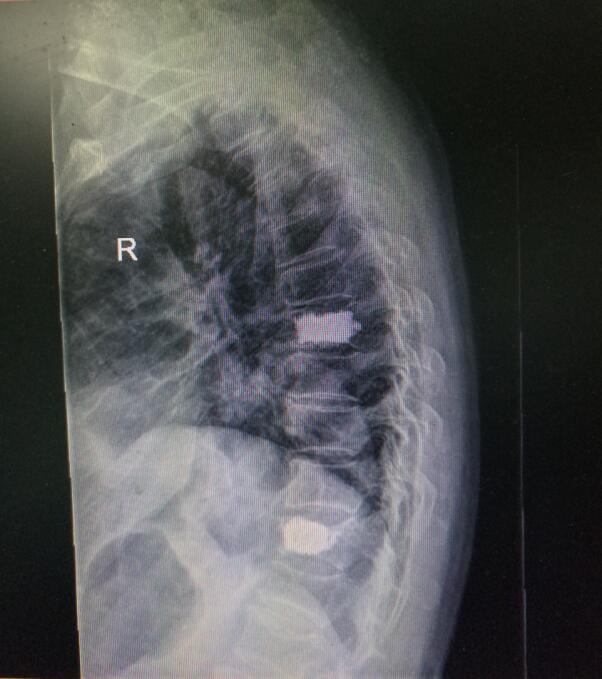

術(shù)后DR(數(shù)字化的x射線)